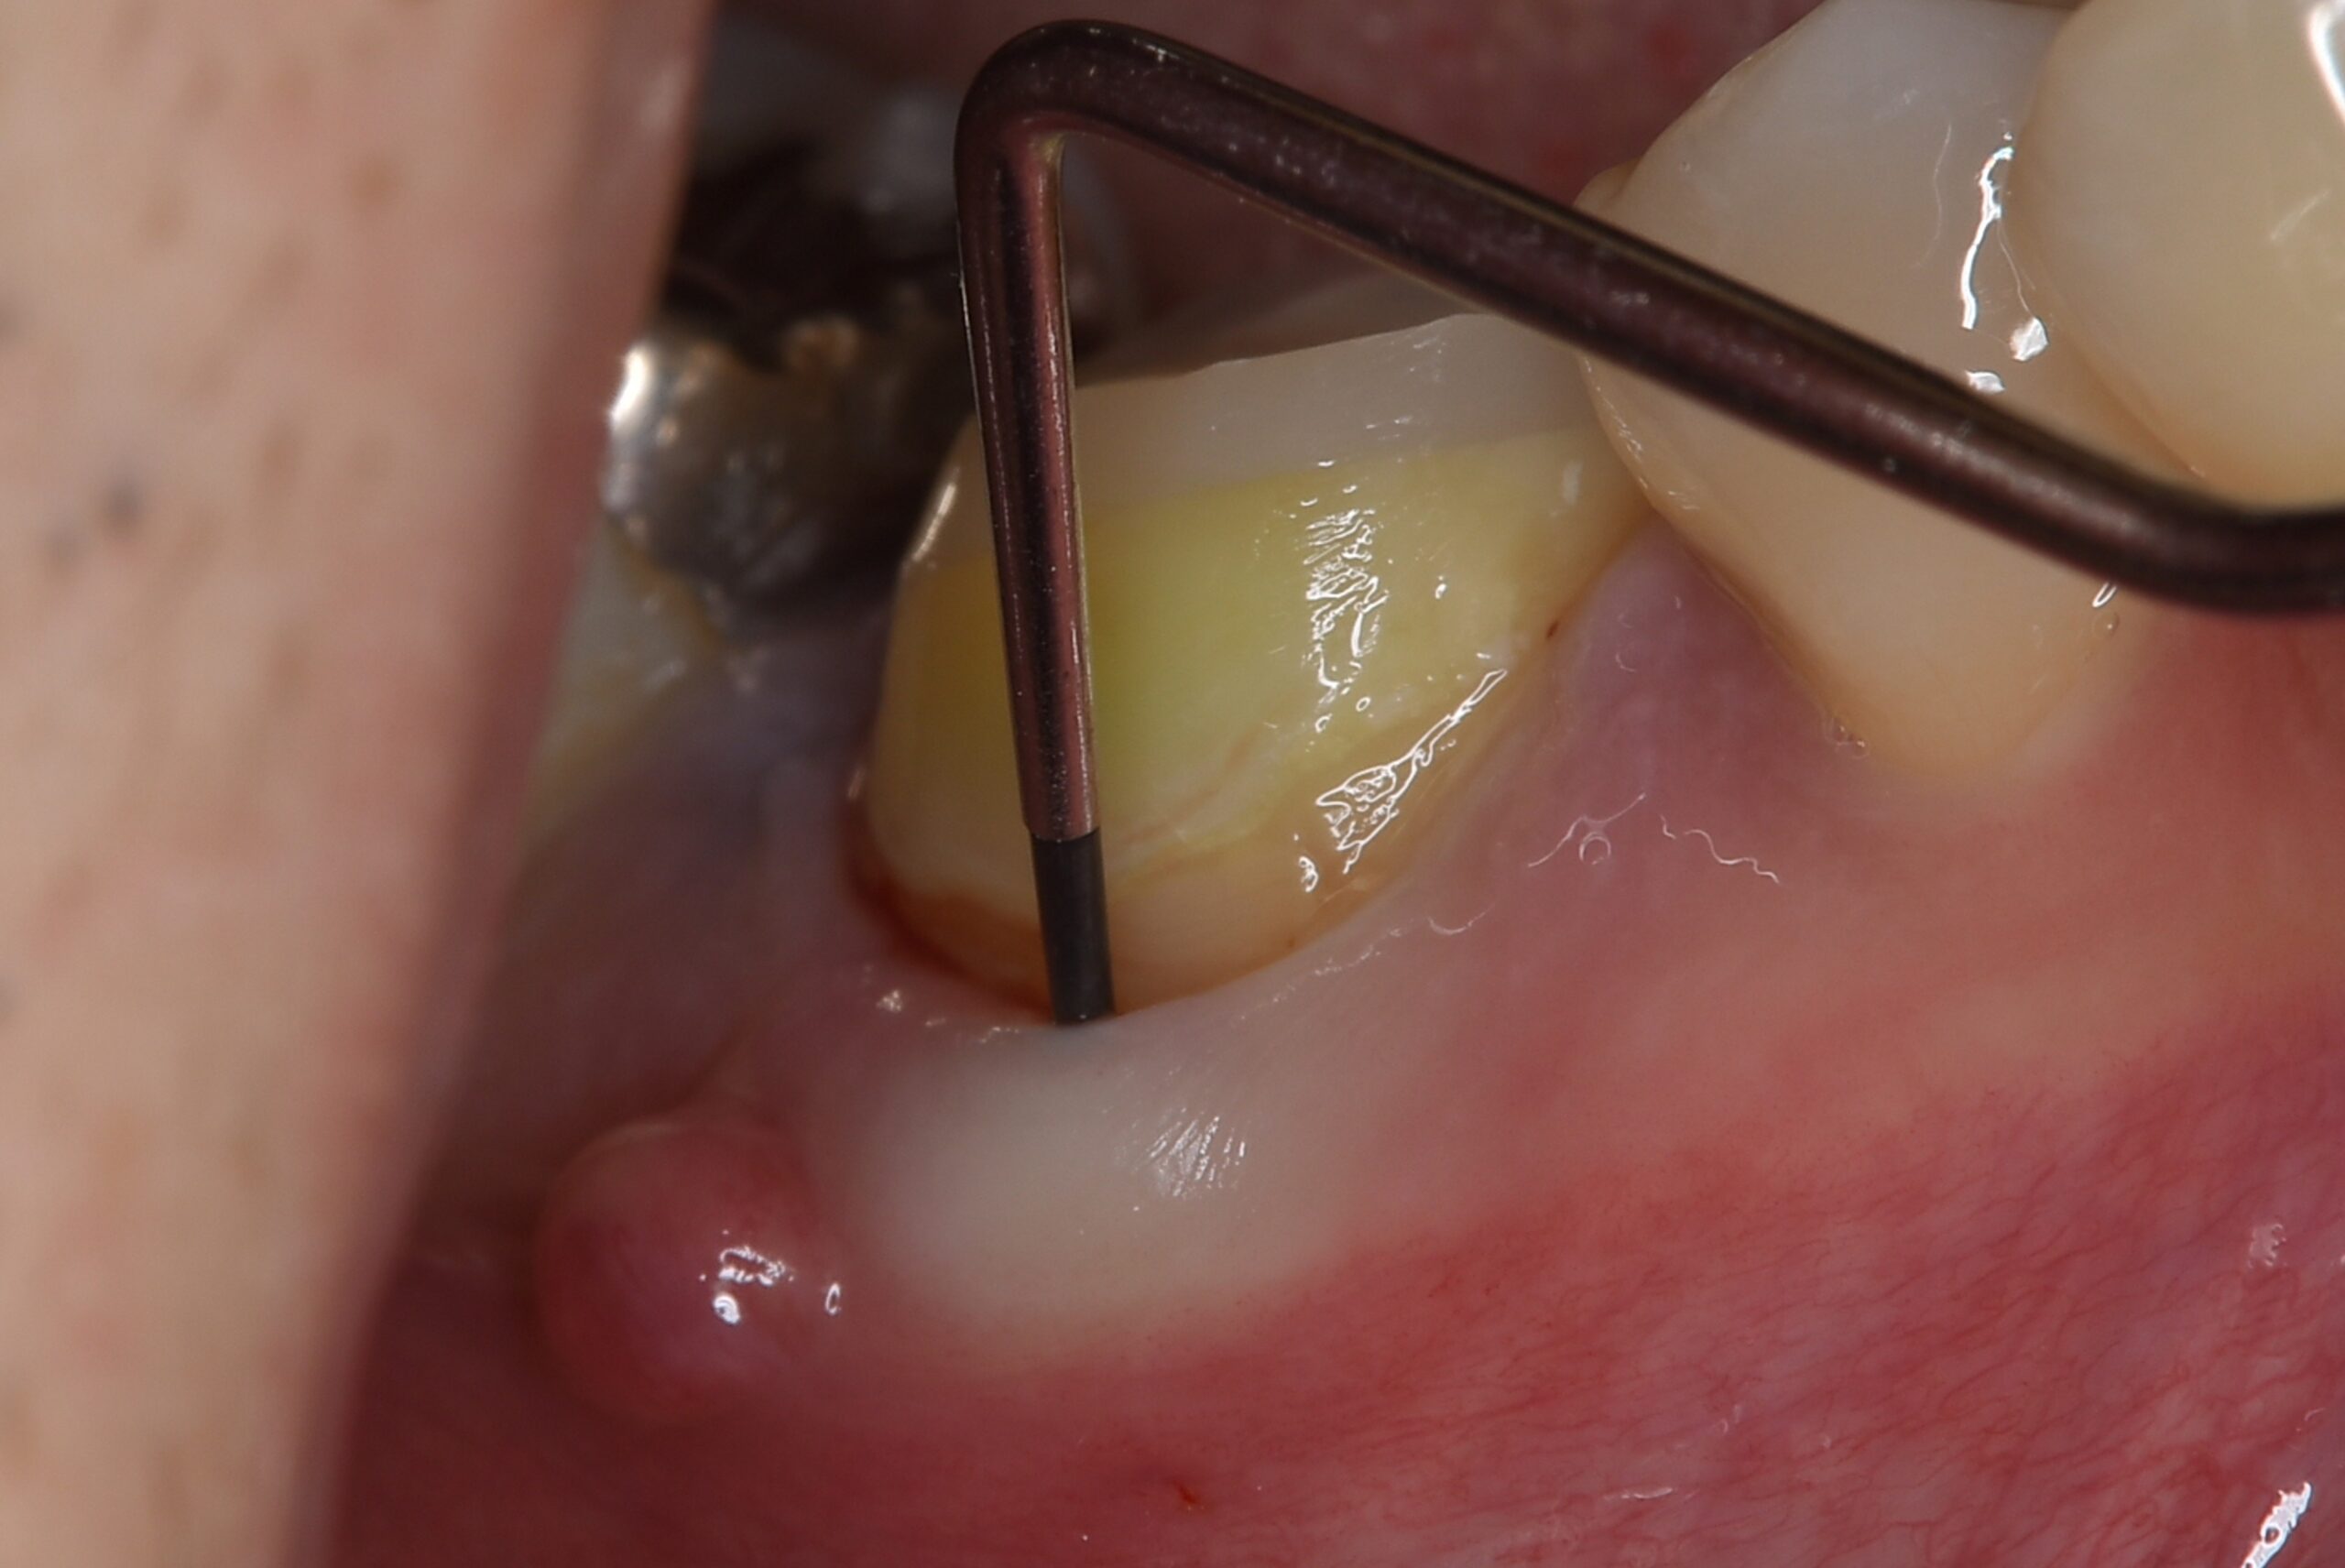

| 来院時の主訴 | 「他院で治療後、器具が歯の中で折れてしまったと言われた。治療の続きからお願いしたい。」 |

| 医院の診断 | 歯根の湾曲、人為的破折ファイルの存在 |

4.5mm以上の破折ファイルは除去しにくいと言われています。 今回は折れてしまった破折ファイルを事前にレントゲンでチェックした所4.57mmありました。破折ファイルはループと言われる特殊な器具を用いて短時間で除去することができました。 |